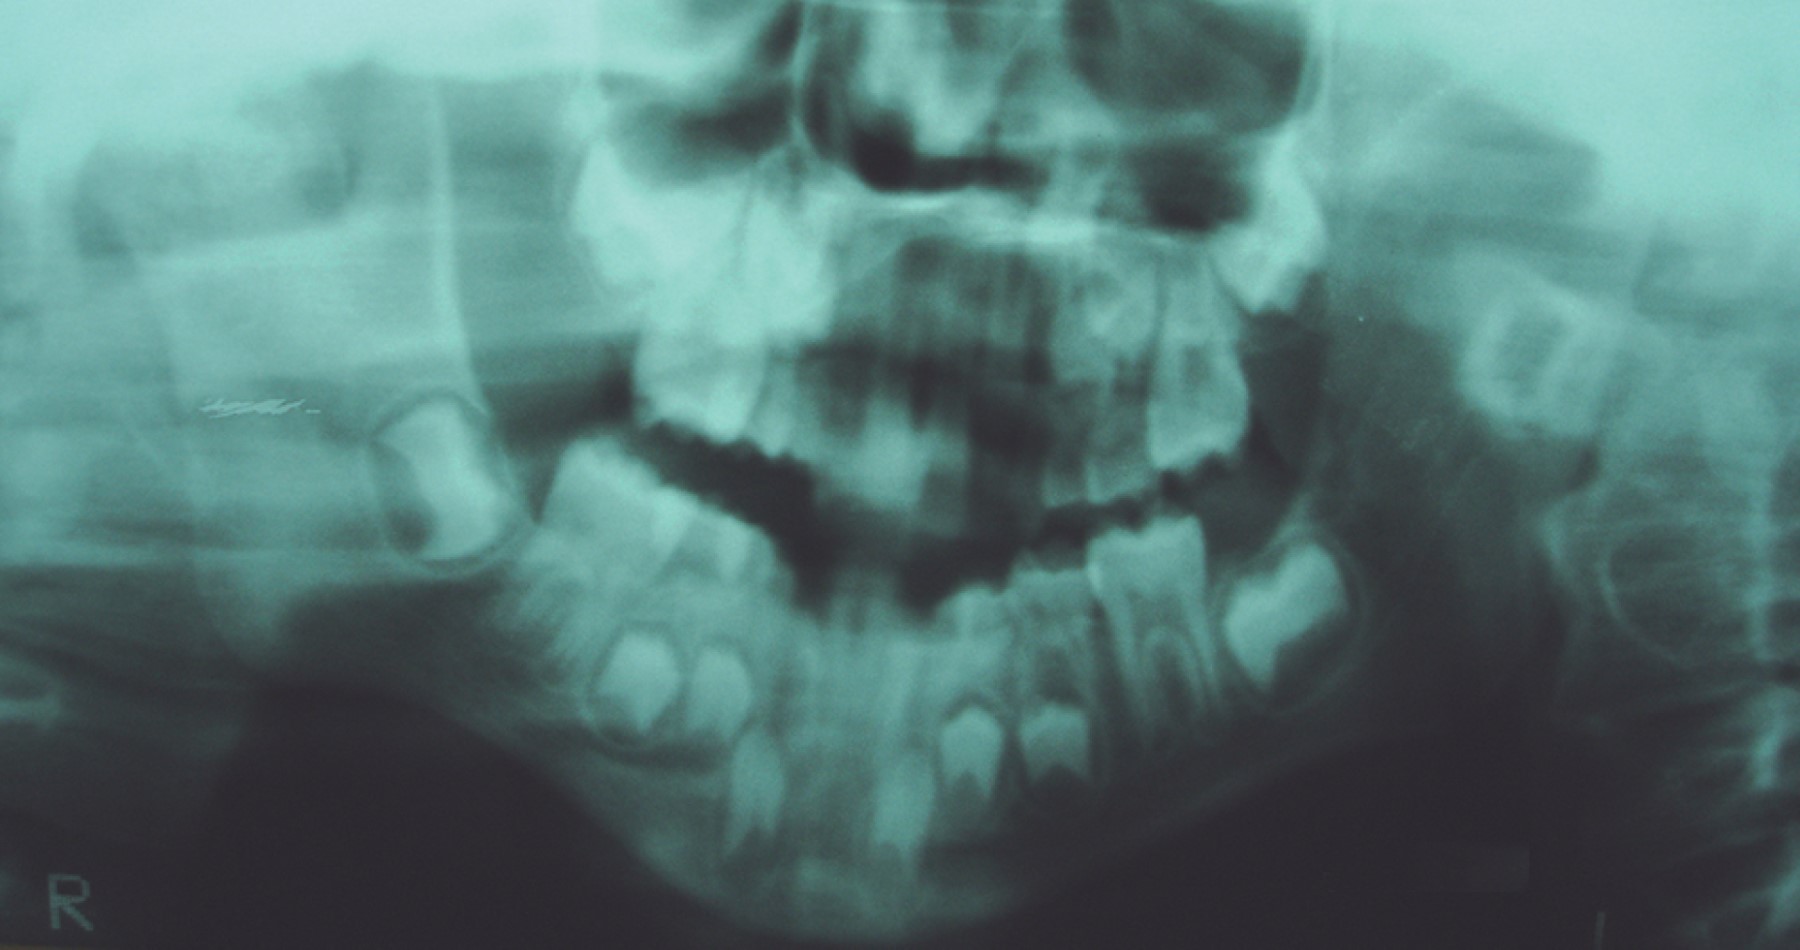

Se trata de paciente masculino de siete años de edad atendido en la Unidad Médica de Alta Especialidad (UMAE) No. 71 del Instituto Mexicano del Seguro Social, en la ciudad de Torreón, Coahuila, México. Acude por presentar imposibilidad de la apertura bucal desde la edad de cinco años, teniendo como único antecedente de importancia traumatismo facial al estar jugando y caer de su propia altura, evolucionando con progresiva limitación de apertura bucal hasta no poder abrirla en lo absoluto. A la exploración física, nula apertura bucal, aspecto facial con mínima alteración estética, micrognatia mandibular sin impacto estético importante (Figura 1). La radiografía inicial muestra anquilosis temporomandibular bilateral (Figura 2). Bajo anestesia general, intubación nasal con fibroscopio, se realiza liberación bilateral de anquilosis temporomandibular eliminando fragmentos óseos anquilosados y colocando prótesis metálicas de cavidad glenoidea de aleación cromo, cobalto, molibdeno (Figura 3), logrando adecuada apertura bucal sin complicaciones qué comentar (Figura 4). A la edad de 11 años se colocan prótesis metálicas de cóndilo de manera bilateral del mismo metal y mentoplastia de avance. Radiografía del paciente a la edad de 23 años (Figura 5).

Figura 2